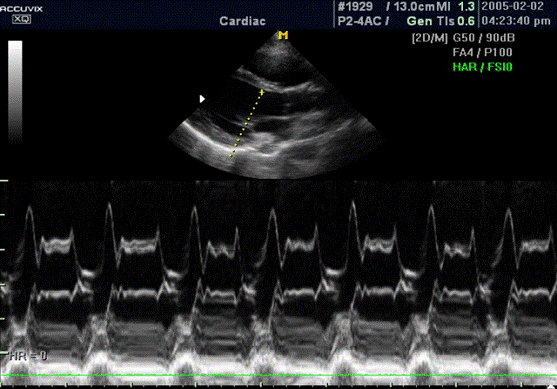

ÏÐÈËÎÆÅÍÈÅ 5

Ðèñ. 4. Óëüòðàçâóêîâîé ìåòîä èññëåäîâàíèÿ ñåðäöà.